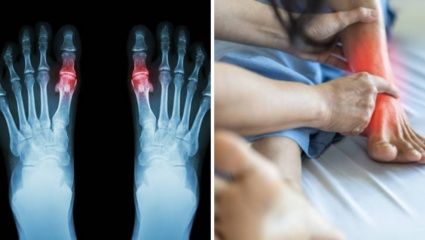

Home Remedy : थंडीत हाडे आणि सांध्यांमधील वेदना दुपटीने जाणवू लागतात. याचे मूळ कारण म्हणजे शरीरात वाढणारे युरिक अ‍ॅसिड. काही पदार्थांना आहारातून निष्कासित करून तुम्ही शरीरातील युरिक अ‍ॅसिडचे प्रमाण कमी…

सांध्यांमध्ये जमा झालेले युरिक ॲसिड कमी करण्यासाठी आहारात वेगवेगळ्या भाज्यांचे सेवन करावे. भाज्यांच्या सेवनामुळे शरीरातील विषारी घटक सहज बाहेर पडून जातील. जाणून घ्या सविस्तर.

सकाळी उठल्यानंतर बऱ्याचदा सांध्यांमध्ये वेदना वाढणे, कंबर दुखी, पाठदुखी, हाडांमध्ये वाढलेल्या वेदना इत्यादी अनेक समस्या उद्भवू लागतात. शरीरात युरिक अ‍ॅसिडची पातळी वाढल्यानंतर हाडांमध्ये वेदना वाढू लागतात. संधिवाताची समस्या उद्भवल्यानंतर संपूर्ण…

रक्तात वाढलेली युरिक ॲसिडची पातळी नियंत्रणात ठेवण्यासाठी आहारात वेगवेगळ्या भाज्यांचे सेवन करावे. भाज्यांच्या सेवनामुळे शरीराला अनेक फायदे होतात. जाणून घ्या सविस्तर.

हिवाळा जवळ आला की सांधेदुखी वाढते. थंडीच्या काळात युरिक अ‍ॅसिडच्या रुग्णांनी विशेष काळजी घ्यावी. शिवाय, या ऋतूत काही भाज्या खाल्ल्याने युरिक अ‍ॅसिडची समस्या वाढू शकते, जाणून घ्या अधिक माहिती

सांध्यांमध्ये वाढलेल्या वेदना कमी करण्यासाठी आणि गाउटपासून सुटका मिळवण्यासाठी आहारात या भाज्यांचे अजिबात सेवन करू नये. या भाज्यांच्या सेवनामुळे रक्तात प्युरीनची पातळी वाढते आणि शरीराला हानी पोहचते.

सांध्यांमध्ये साचून राहिलेले युरिक ऍसिड नष्ट करण्यासाठी आहारात वेगवेगळ्या भाज्या आणि फळांचे सेवन करावे. यामुळे शरीराला सुद्धा अनेक फायदे होतात. जाणून घ्या नियमित कोणत्या भाज्या खाव्यात.

चुकीच्या आहारामुळे शरीरात युरिक अ‍ॅसिड जमा होत, जे वेळीच बाहेर पडलं नाही तर शरीरात खडे तयार होण्याची शक्यता असते. काही घरगुती पदार्थांचे सेवन हे युरिक अ‍ॅसिड शरीराबाहेर काढण्यास मदत होते,…

धावपळीच्या जीवनशैलीमुळे प्रत्येक व्यक्ती कोणत्या ना कोणत्या आरोग्यासंबंधित समस्यांनी त्रस्त आहेत. त्यातील अनेकांमध्ये दिसून येणारी समस्या म्हणजे शरीरात वाढलेले उच्च यूरिक अ‍ॅसिड. कोलेस्ट्रॉल, मधुमेह आणि उच्च यूरिक अ‍ॅसिड वाढल्यानंतर शरीरात…

युरिक अ‍ॅसिडचे क्रिस्टल्स सांध्यामध्ये जमा होतात ज्यामुळे समस्यांना तोंड द्यावे लागते. जर तुम्हाला युरिक अ‍ॅसिडचे प्रमाण जास्त असेल तर या डाळी खाणे टाळा. जास्त प्युरिन असलेल्या या डाळींचे सेवन करणे…

मागील काही काळापासून अनेकांना युरिक अ‍ॅसिडची समस्या फार सतावत आहे. हे समस्या वेळीच नियंत्रणात केली नाही तर यामुळे आरोग्याच्या अनेक समस्या निर्माण होऊ शकतात. यामुळे गाउट, मूत्रपिंडात खडे आणि सांध्यांमध्ये…

आहारात होणाऱ्या छोट्या मोठ्या बदलांमुळे शरीरात युरिक अ‍ॅसिड वाढू लागते. शरीरात वाढलेली युरिक अ‍ॅसिडची पातळी आरोग्यासाठी अतिशय घातक ठरते. यामुळे सांध्यांमध्ये वेदना वाढणे, गाऊट किंवा हाडांना सूज येण्याची जास्त शक्यता…

शरीरात वाढलेले युरिक ॲसिड नियंत्रणात ठेवण्यासाठी आहारात हिरव्या चटणीचे सेवन करावे. या चटणीच्या सेवनामुळे युरिक ॲसिडची पातळी कमी होते आणि आरोग्य सुधारण्यास मदत होते. जाणून घ्या हिरवी चटणी खाण्याचे फायदे.

शरीरात वाढलेल्या युरिक अ‍ॅसिडमुळे संधिवात, हाडांमध्ये गाऊट जमा होणे, बोटांमध्ये वेदना वाढणे इत्यादी अनेक समस्या उद्भवू लागतात. रोजच्या आहारात प्युरीन युक्त पदार्थांचे जास्त सेवन केल्यामुळे सांध्यांमध्ये किंवा शरीराच्या हाडांमध्ये युरिक…

शरीरात वाढलेल्या युरिक अ‍ॅसिडमुळे सांध्यांमध्ये वेदना वाढणे, हातापायांना मुंग्या येणे इत्यादी अनेक समस्या उद्भवू लागतात. या समस्यांपासून आराम मिळवण्यासाठी आहारात या पदार्थांचे नियमित सेवन करावे.

शरीरात यूरिक अ‍ॅसिडची पातळी वाढल्यानंतर सांध्यांमध्ये वेदना होणे, संधिवात किंवा आरोग्यासंबंधित इतरही समस्या उद्भवू लागतात. यूरिक अ‍ॅसिडची पातळी वाढल्यानंतर शरीरात ही गंभीर लक्षणे दिसून येतात.

युरिक अ‍ॅसिडची समस्या झपाट्याने वाढत आहे. याचे सेवन अनेक समस्यांना आमंत्रण देत असते. अशात काही पदार्थांचे सेवन करून तुम्ही शरीरात वाढलेले युरिक अ‍ॅसिड नियंत्रणात करू शकता.

जर तुम्हालाही घाणेरड्या युरिक अ‍ॅसिडचा त्रास होत असेल, तर येथे जाणून घ्या की युरिक अ‍ॅसिड कमी करण्यासाठी आहारात कोणत्या गोष्टींचा समावेश करता येईल. हे पदार्थ शरीराला आतून स्वच्छ करतात.

शरीरात युरिक अ‍ॅसिडची पातळी वाढल्यानंतर सांध्यांमध्ये क्रिस्टल जमा होऊ लागतात.यामुळे गुडघे दुखू, सांध्यांना आलेली सूज किंवा वेदना वाढण्याची शक्यता असते.या वेदना कमी करण्यासाठी नियमित आलं आणि ओव्याचे पाण्याचे सेवन करावे.